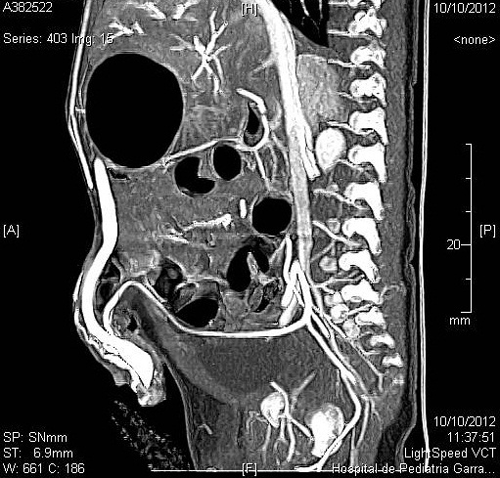

A 20-day-old male neonate with an umbilical hernia was referred to our hospital because of persistent wet umbilicus. Umbilical examination showed a 2 cm diameter umbilical hernia and a long epithelialized pulsatile cord with granulomatous tissue at its end (Fig. 1). Palpable thrill was note at the midportion of the umbilical cord. Doppler ultrasonography revealed a mass at the end of the umbilical cord harboring dilated blood vessels with turbulent blood flow (Fig. 2). This vascular mass continued to the umbilical vein, which was dilated and flowed into the liver. Abdominal contrast-enhanced computed tomography revealed umbilical AVM; the umbilical arteries were patent from both internal iliac arteries, flowed into the mass directly at the end of the umbilical cord, and the dilated umbilical vein flowed out from the mass, continuing from the umbilicus to the umbilical part of the portal vein in the liver (Fig. 3, 4).

Figure 3: Umbilical arteries arising from both internal iliac arteries, flowing into the mass directly at the end of the umbilical cord. |